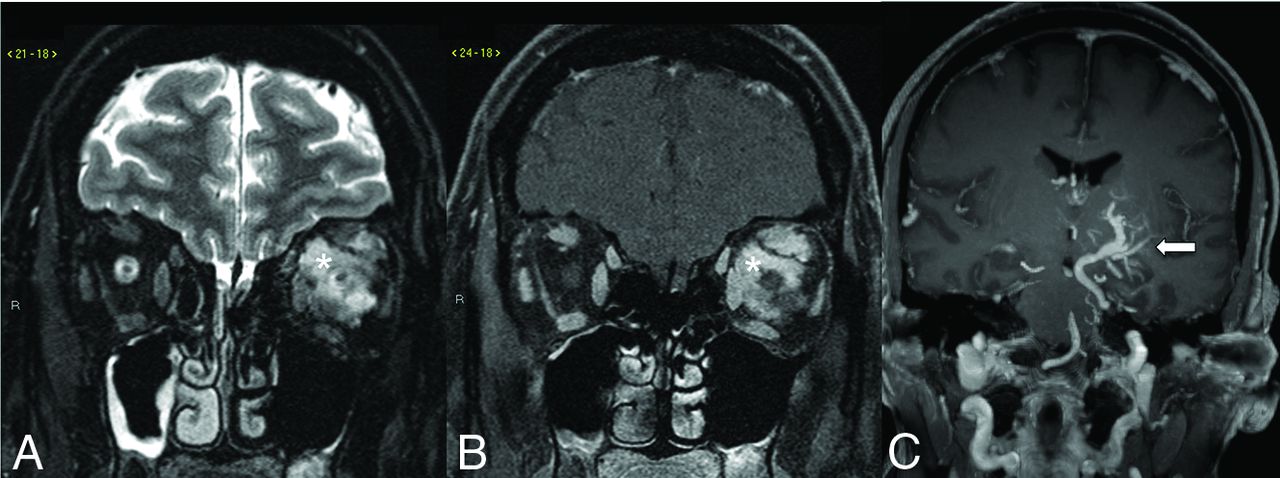

Basal ganglia and deep cerebellar nuclei are regions of the brain with higher metabolic demands. The presence of a DVA in these locations across time may lead to increased mineralization within the affected deep gray matter structure (Fig 4).20 Metabolic abnormalities can also be encountered in the venous drainage territory of a DVA. A small case series of 22 patients found that 76% of DVAs studied had metabolic changes on FDG-PET/CT scans in the form of hypometabolism, which was significantly more common in older patients (Fig 5).21 A subsequent larger study with 54 patients with 57 DVAs showed evidence of metabolic abnormalities in 38% of patients; in this study, hypometabolism was more common in DVAs draining gray matter rather than white matter.22 Hypometabolism has been reported in regions corresponding to neurologic symptoms; for example, hypometabolism was seen in the visual tracts in patients with visual symptoms and a corresponding DVA.23 Most interesting, structural abnormalities (ie, WMH) were not seen in these patients with abnormalities on functional images.21,22 Again, this finding is supportive of the notion that DVAs have a less robust venous drainage pathway.

Noncontrast CT of the head (A and B) shows dystrophic calcification of the anterior right putamen and pulvinar of the thalamus (arrows). CTV MIP sagittal image (C) shows a right basal ganglia DVA (arrowheads) with the collector vein draining into the ipsilateral internal cerebral vein (arrows).

Most DVAs have sporadic and isolated findings; however, DVAs can be part of a syndromic feature in patients with mutations in either shared RAS-MAPK and PI3K/AKT/mTOR intracellular signaling pathways, which are drivers of the phenotypic development of vascular malformations and tumors.33 Most notably, syndromes associated with DVAs include blue rubber bleb nevus syndrome (BRBNS), constitutional mismatch repair deficiency syndrome (CMMRD), and the more recently described cerebrofacial venous metameric syndrome (CVMS). BRBNS is mostly sporadic, but a few reported cases show autosomal dominant inheritance caused by TIE2/TEK somatic mutations, which encode the endothelial cell–specific tyrosine kinase receptor that functions via the PI3K/AKT/mTOR signaling pathway. The syndrome is characterized by multiple rubbery venous malformations found in the skin, brain, and visceral organs. The correlation between DVAs and BRBNS was underestimated in the older literature due to imaging techniques and the nonunified use of DVA as descriptive terminology.34 CMMRD is also known to be associated with DVAs. It is an autosomal recessive biallelic (homozygous) germline mutation in the mismatch repair genes (MLH1, MSH2, MSH6, and PMS2).35 CMMRD manifests as neoplastic and non-neoplastic processes such as a DVA. Oncologic manifestations of the CMMRD are variable in the CNS, along with intestinal tumors and hematologic malignancy.35 There is a robust association of CMMRD with DVAs, which has been suggested to be a potential quantifiable factor for CMMRD, and this is further support for a genetic basis for DVAs.35 In CVMS, facial venous malformations have a 20%–28% association with DVAs, and most of the DVAs are ipsilateral and in the same metamere as the superficial venous malformation (Fig 11).36,37 The association between DVAs and head and neck venous malformations may share a common developmental pathogenesis.

CVMS in a patient with a left orbital venous malformation depicted on the coronal T2-weighted fat saturated (A) and coronal post-gadolinium-enhanced T1-weighted fat saturated (B) images, which show an infiltrative T2-weighted hyperintense intraconal lesion with avid contrast enhancement (asterisk). Coronal gadolinium-enhanced T1-weighted image (C) reveals a large left basal ganglia DVA (arrow) with the collector vein draining in the left superior petrosal sinus.